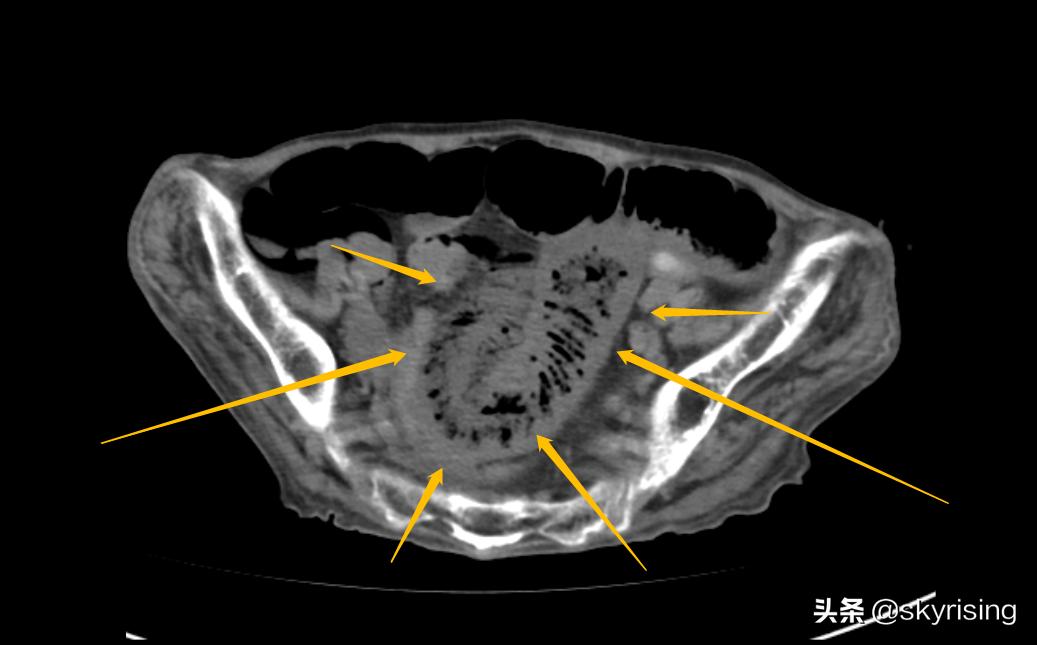

下图黄色箭头所示小肠回肠肠襻呈U型改变,肠管扩张,肠壁增厚,肠壁间见垂直线性气体密度影。这是典型肠系膜血管栓塞的典型表现,可能是动脉也可能是静脉,需要结合增强检查。

以上CT表现,小肠空肠走行区扩张、积液、积气、多个气液平面形成,符合肠梗阻典型表现;肝脏树枝状气体及小肠肠壁间气体密度影,需要警惕肠系膜血管栓塞可能,动脉及静脉栓塞均可能;结肠走行区管壁增厚、密度增高,符合出血表现,提示静脉栓塞可能性远大于动脉栓塞。

3、汇总分析:老年患者,病史复杂,基础状态差,胆囊切除术后、斜疝修补术后、气管切开术后,CT平扫小肠肠管积液、积气、扩张、多个气液平面,符合肠梗阻典型表现,至于原因,术后肠管黏连可能性大,需要警惕肿瘤性并病变可能。肝脏积气及小肠肠壁间积气,考虑门静脉积气并小肠肠壁间积气,符合肠系膜血管栓塞表现;结肠走行区管壁增厚、密度增高,提示出血性梗死可能,需要考虑静脉性梗死,以肠系膜上静脉梗死可能性大。